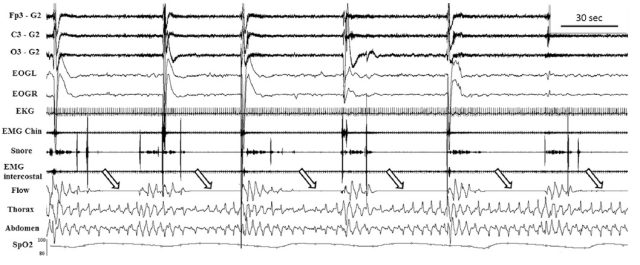

此外,患者还进行了超声心动图,发现存在 PFO,左室射血分数为 62%,左室舒张末期直径为 57 mm,右室无明显异常。自身免疫相关的筛查及 24 小时长程心电图无明显异常。随后,患者在入院后第 15 天进行了多导睡眠图监测,结果显示患者存在持久的呼吸暂停(如图 2)。

图 2:一段 5 分钟的多导睡眠图,显示阻塞性呼吸暂停